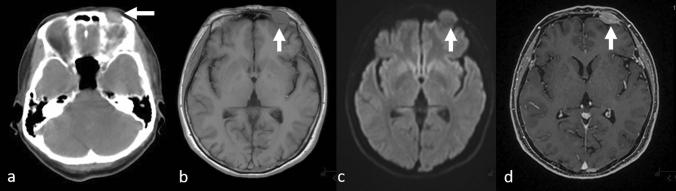

Although metastases found during head magnetic resonance imaging (MRI) are not limited to metastatic brain tumors, the MRI is a very common method for "brain metastasis screening," a modality that is being increasingly performed. In this review, we describe MRI findings of nonbrain metastases and discuss ways to avoid missing these lesions. Metastatic cranial bone tumors are among the most common nonbrain metastatic lesions found on head MRI, followed by leptomeningeal carcinomatosis. The other less-frequent metastatic lesions include those in the ventricle/choroid plexus, the pituitary gland and stalk, and the pineal gland. Metastases in the head and neck area, as well as cranial and intracranial lesions, should be carefully evaluated. Furthermore, direct geographical invasion, perineural spread, and double cancers should also be considered. While it is important to recognize these metastatic lesions on MRI, because they may necessitate a change in treatment strategy that could lead to an improvement in prognosis due to early introduction of therapy, nonbrain lesions should also be given greater attention, given the increasing survival of patients with cancer and advances in MRI technology, such as contrast-enhanced-3D T1-weighted imaging.

尽管头部磁共振成像(MRI)检查发现的转移不限于脑转移瘤,但 MRI 是一种非常常见的“脑转移筛查”方法,这种方法的应用越来越广泛。在这篇综述中,我们描述了非脑部转移瘤的 MRI 表现,并讨论了避免遗漏这些病变的方法。转移性颅骨肿瘤是头部 MRI 上最常见的非脑转移病变之一,其次是软脑膜癌病。其他较少见的转移性病变包括脑室/脉络丛、垂体及其柄和松果体转移瘤。头颈部、颅腔和颅内病变应仔细评估。此外,还应考虑直接的地理侵犯、神经周围扩散和双癌。虽然在 MRI 上识别这些转移瘤很重要,因为它们可能需要改变治疗策略,通过早期引入治疗来改善预后,但鉴于癌症患者的生存率提高和 MRI 技术的进步,如增强-3D T1 加权成像,也应更加关注非脑部病变。